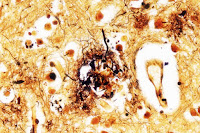

In an interview with Rudolph Tanzi he states, “In Alzheimer’s disease, there are three pillars of pathology. There’s the plaque, the tangles, and inflammation.”

| Under the microscope |

His explanation talks of inflammation being the fuel that increases the genetic possibilities for plaque and tangles which destroys cells in the brain. We have not been able to find medicines to help with these conditions, so for now making good lifestyle changes give us our best hope of dealing with this.